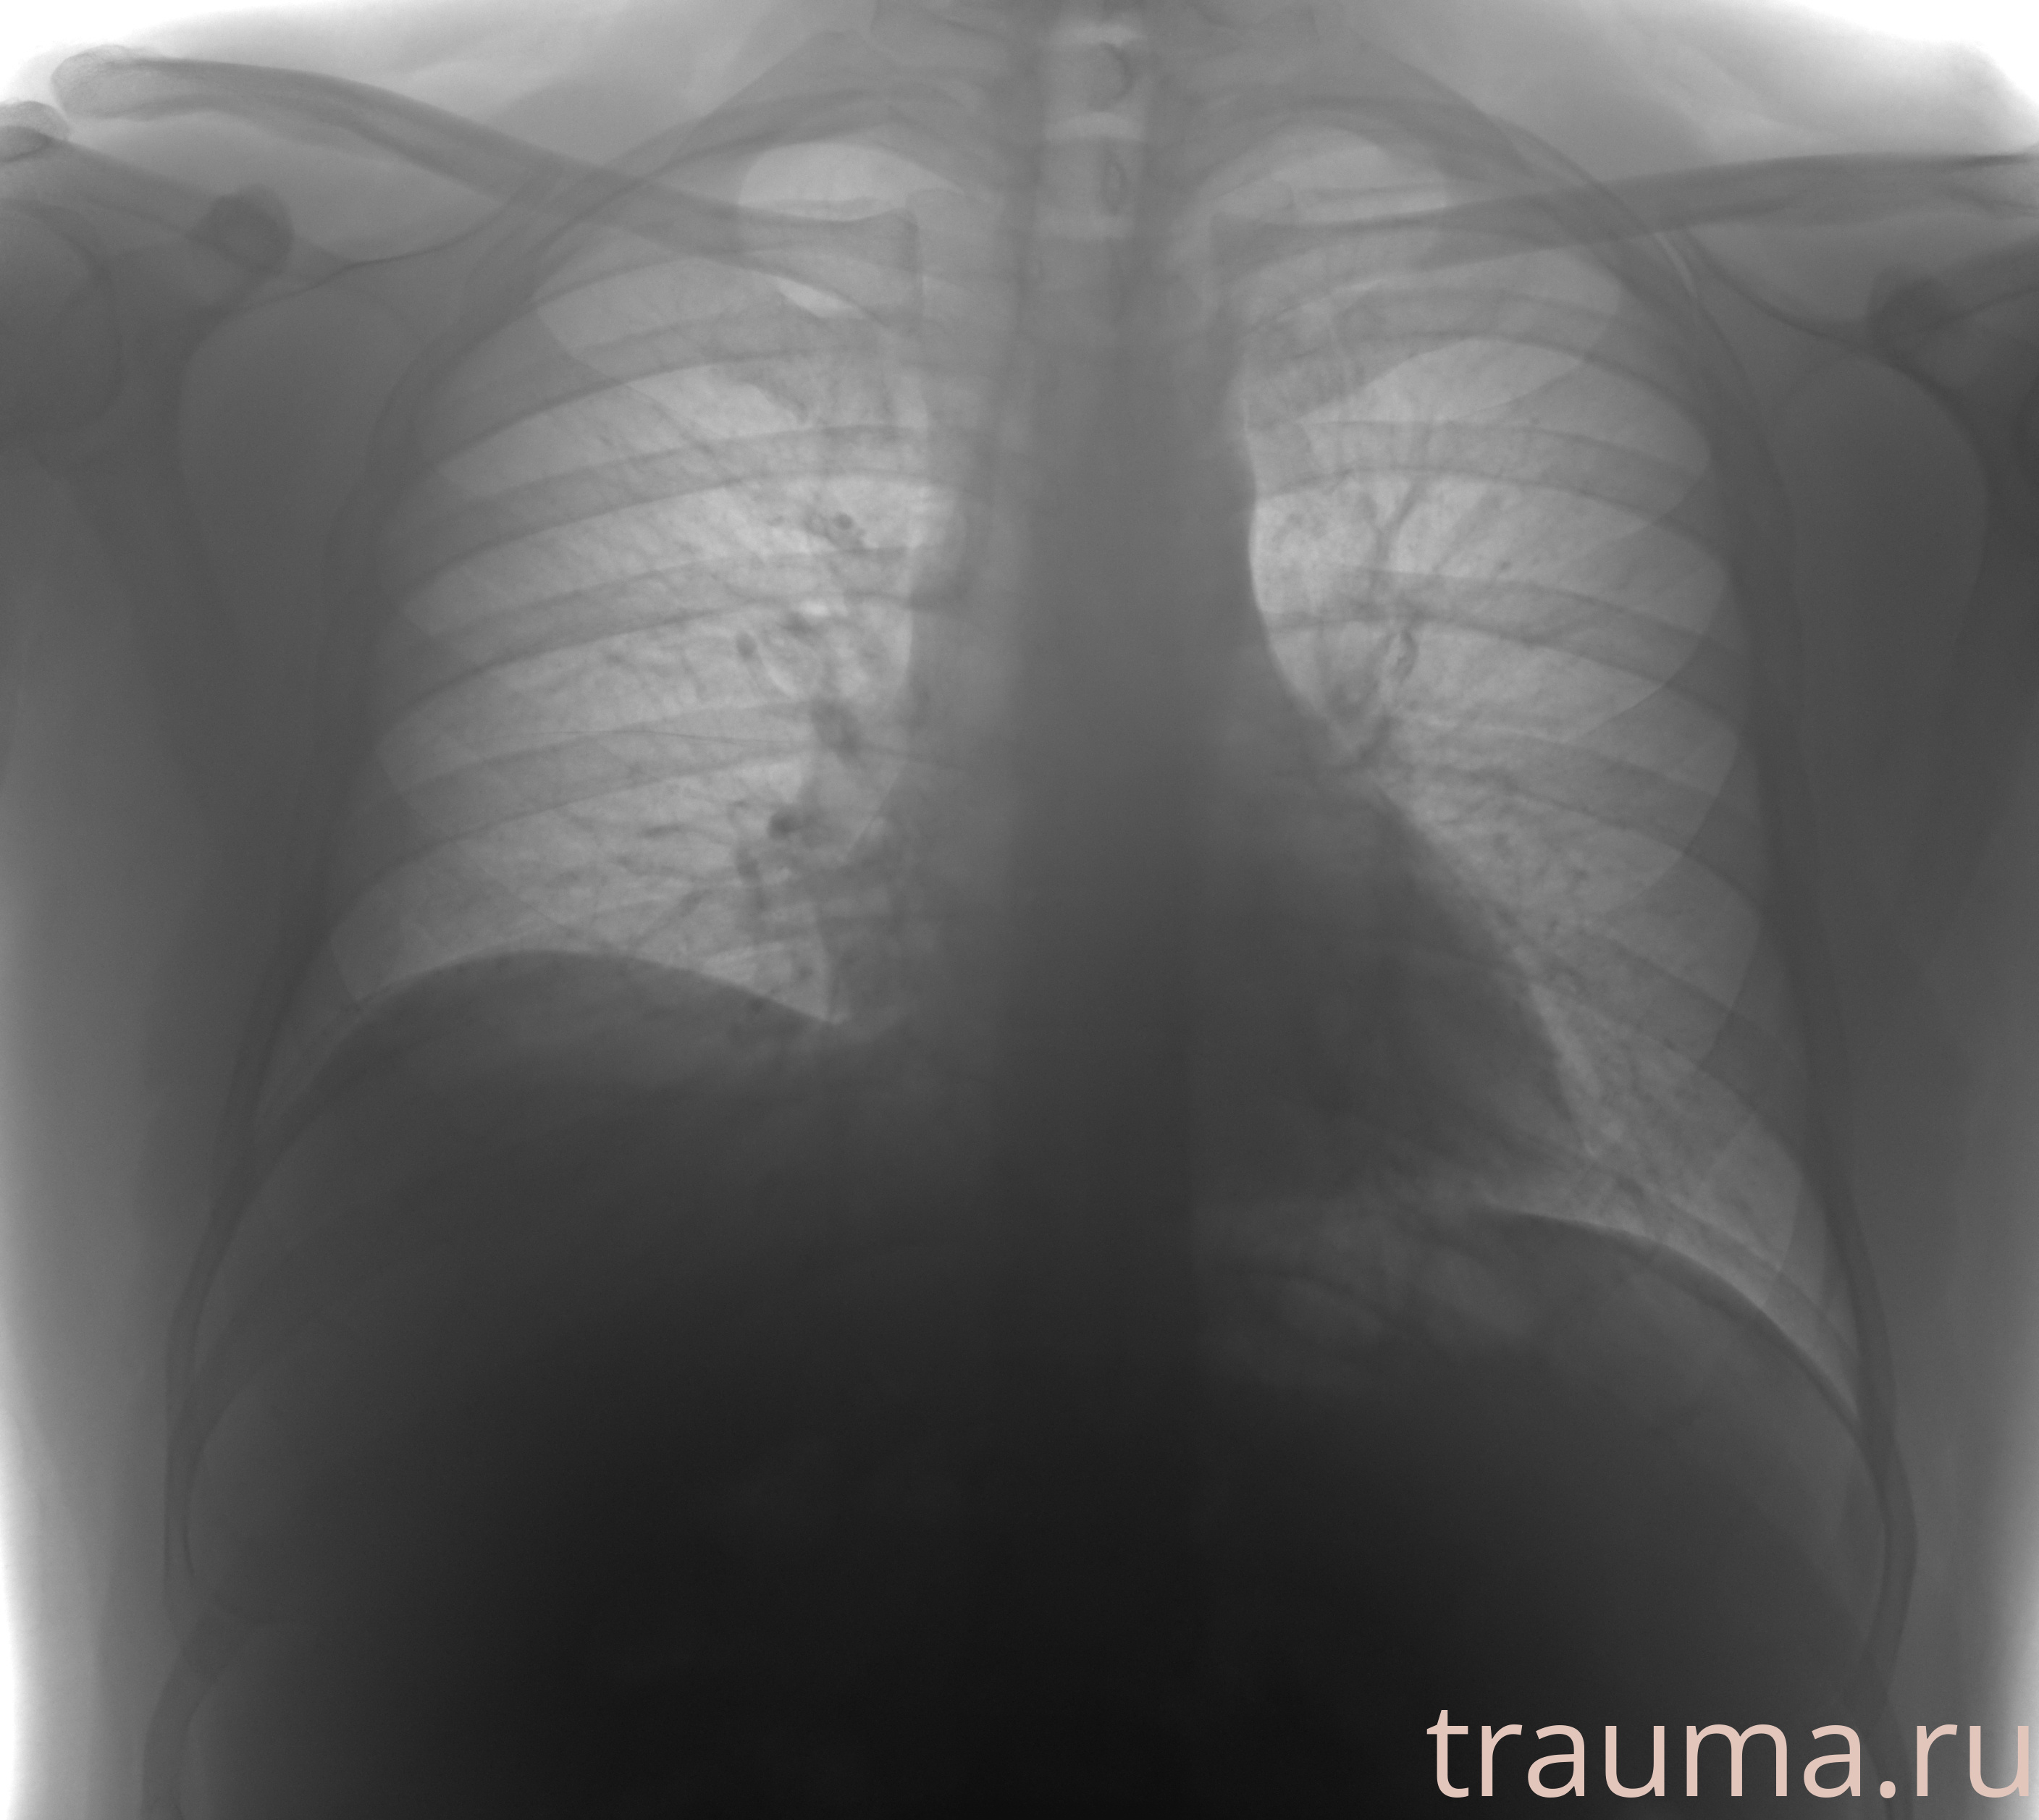

Рентгенограммы

Рентген на дому: по вашему адресу приезжает врач-рентгенолог, травматолог-ортопед с мобильным рентгеновским аппаратом, проводит диагностику травмы или заболевания, делает необходимые рентгенограммы, дает рекомендации по дальнейшему лечению. Получить качественные снимки в домашних условиях возможно благодаря уникальной методике, разработанной МосРентген Центром для института  Склифосовского

при переломе шейки бедра и пневмонии от компании МосРентген Центр - партнера Института имени Склифосовского